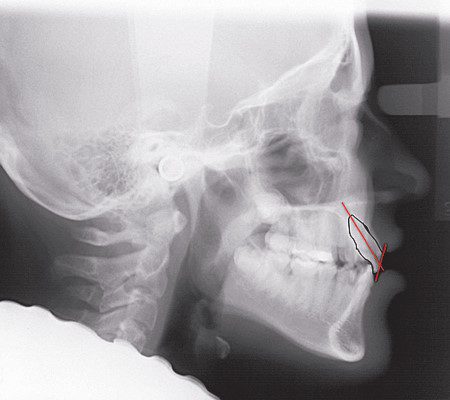

Hình dạng răng không chỉ liên quan đến thân răng lâm sàng mà còn liên quan đến hình thái chân răng và góc tạo bởi thân răng – chân răng. Đây là yếu tố rất quan trọng trong kỹ thuật mắc cài dây thẳng, vì kỹ thuật này dựa trên góc nghiêng của thân răng so với mặt phẳng nhai trên cả ba mặt phẳng không gian.

Nếu góc tạo bởi thân và chân răng quá nhọn thì khi sử dụng mắc cài tiêu chuẩn, có thể dẫn đến:

- Chân răng bị đẩy ra khỏi xương vỏ theo chiều trước sau (lệnh ba), hoặc

- Chân răng bị ép vào răng kế cận theo chiều gần–xa (lệnh hai) (hình 1-40).